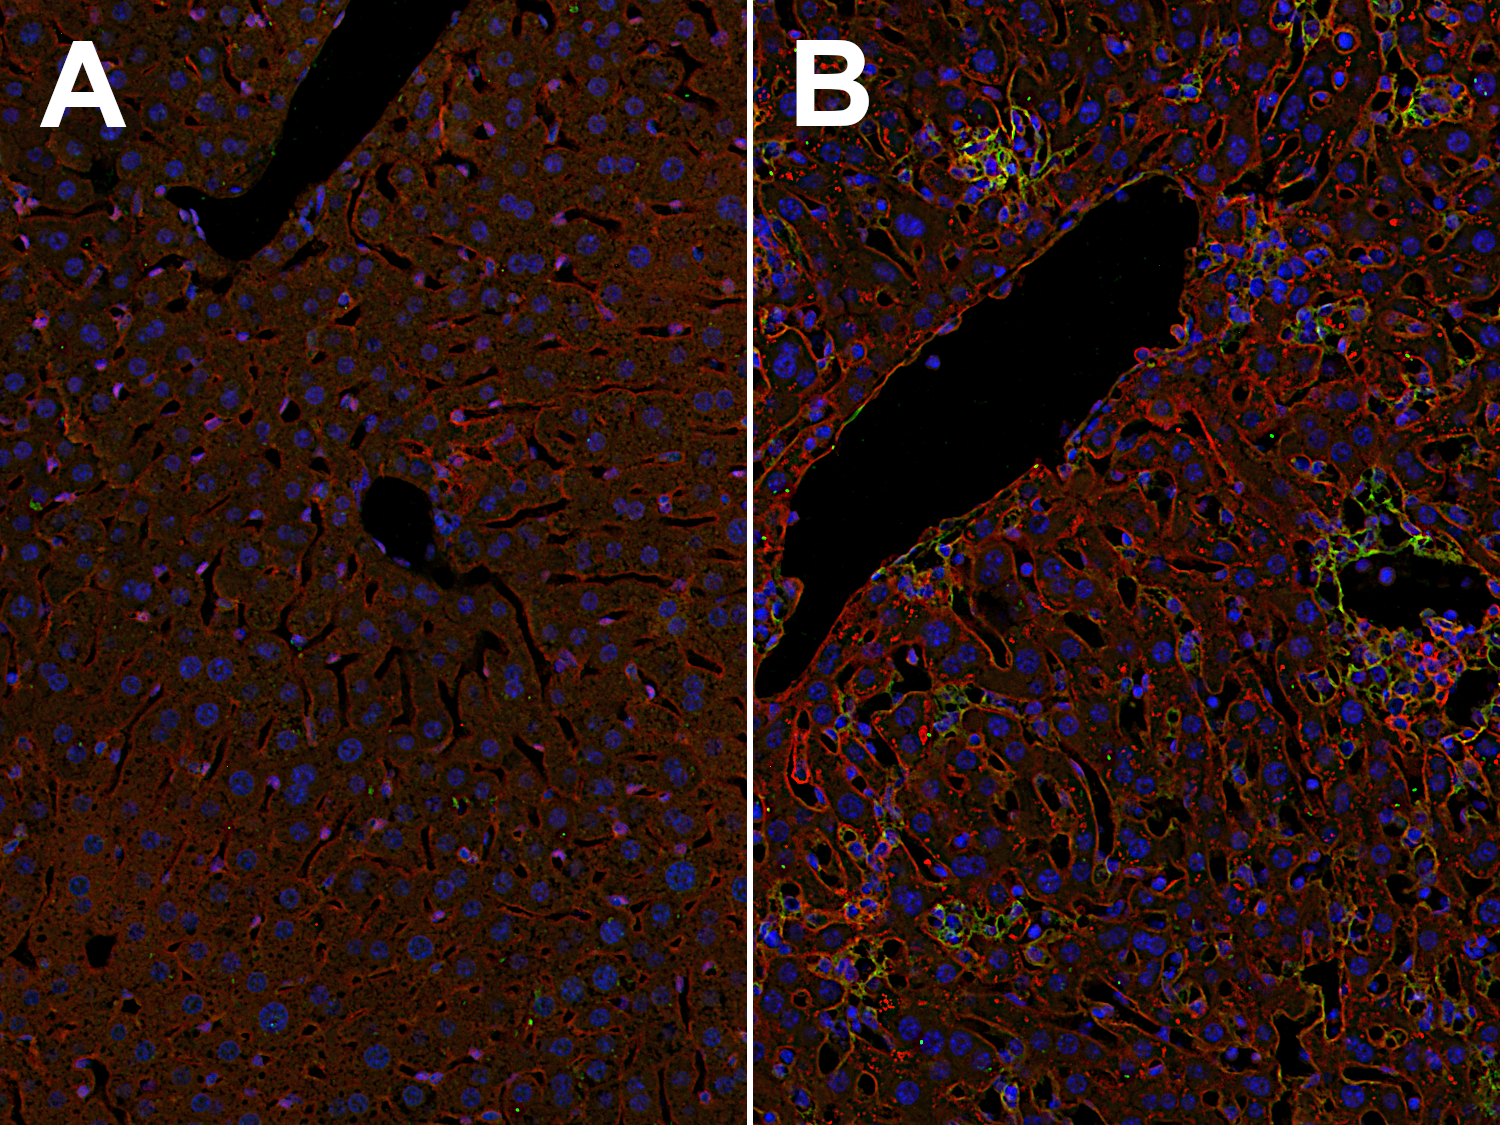

Inflammatory cytokines, including TNFα, IL-1β, and IFNγ, strongly upregulate the expression of ICAM1 and VCAM1, not just on endothelial cells, but also on other cell types, e.g., fibroblasts and inflammatory macrophages (Hosokawa et al., 2006, Wiesolek et al., 2020). Elevated ICAM1 and VCAM1 expression levels are found, for example, on liver sinusoidal endothelial cells and in multifocal mononuclear cell aggregations in the liver of a mouse infected with Toxoplasma (T.) gondii (Figure 2).

Indirect immunostaining of formalin fixed paraffin embedded (FFPE) mouse liver sections of a non-infected mouse (A) and a T. gondii-infected mouse (B) with rabbit anti-ICAM1 antibody (cat. no. HS-532 003, dilution 1:500, red) and guinea pig anti-VCAM1 antibody (cat. no. HS-470 004, dilution 1:500, green). Nuclei have been visualized by DAPI staining (blue).

Figure 2: Elevated ICAM1 and VCAM1 levels on liver sinusoid endothelial cells and in multifocal mononuclear cell aggregations in the liver of a mouse infected with T. gondii. Indirect immunostaining of formalin fixed paraffin embedded (FFPE) mouse liver sections of a non-infected mouse (A) and a T. gondii-infected mouse (B) with rabbit anti-ICAM1 antibody (cat. no. HS-532 003, dilution 1:500, red) and guinea pig anti-VCAM1 antibody (cat. no. HS-470 004, dilution 1:500, green). Nuclei have been visualized by DAPI staining (blue).